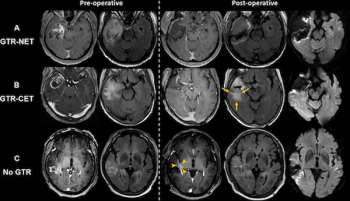

Irrespective of age or O6-methylguanine-DNA methyltransferase (MGMT) promoter methylation status, gross total resection of IDH wild-type glioblastomas was associated with a median overall survival of 32.6 months, according to new MRI research.